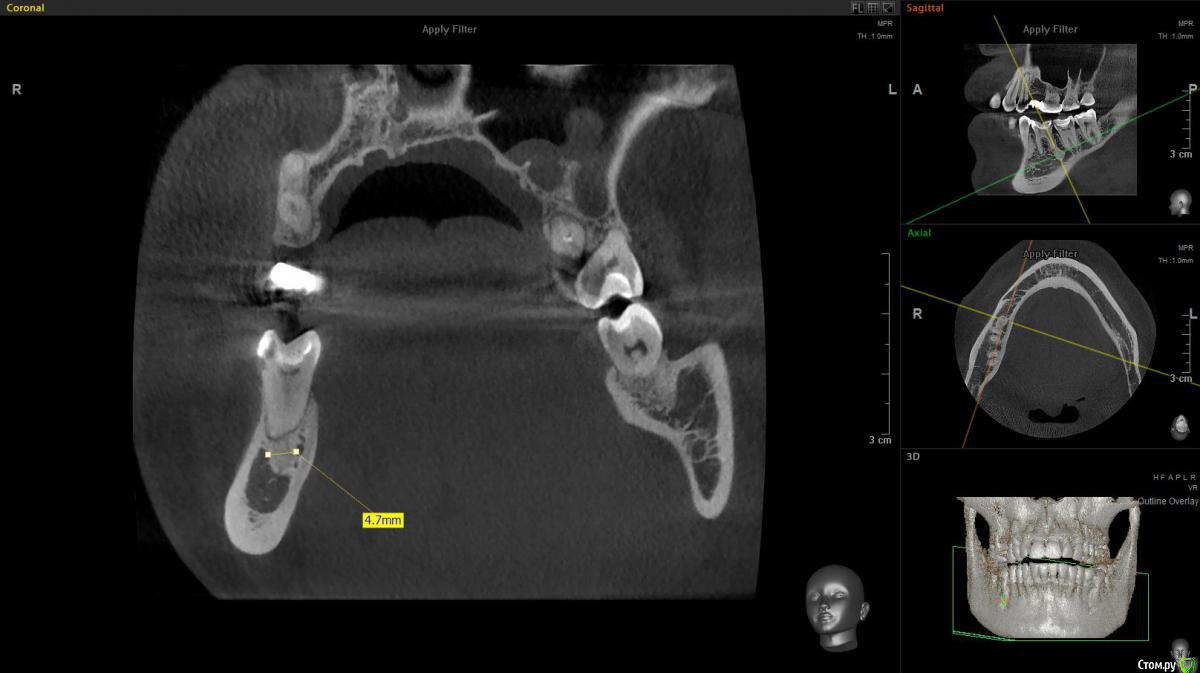

Turalyon Опубликовано 25 февраля, 2020 Поделиться Опубликовано 25 февраля, 2020 Добрый вечер, коллеги. Пациентка 1974 г. р обратилась с жалобами на боль при жевании.Зуб 46 лечен 2 мес. назад по поводу кариеса. Перкуссия +, пальпация в области переходной -, холодовой тест +, чувствительность проходит секунд через 5. В периапикальной имеется затемнение. Без гистологии окончательный диагноз не поставить, однако я предполагаю, что это остеома.Если что, могу кинуть ссылку на кт. Каково ваше мнение касаемо участка затемнения у апекса 46 зуба? 1 Ссылка на комментарий

krokomot Опубликовано 25 февраля, 2020 Поделиться Опубликовано 25 февраля, 2020 Это не остеома, а компактное вещество, вариант строения или аномалия. Ссылка на комментарий

Lodkin666 Опубликовано 26 февраля, 2020 Поделиться Опубликовано 26 февраля, 2020 Эностоз, участок более плотной кости. Забудьте про него. 1 Ссылка на комментарий